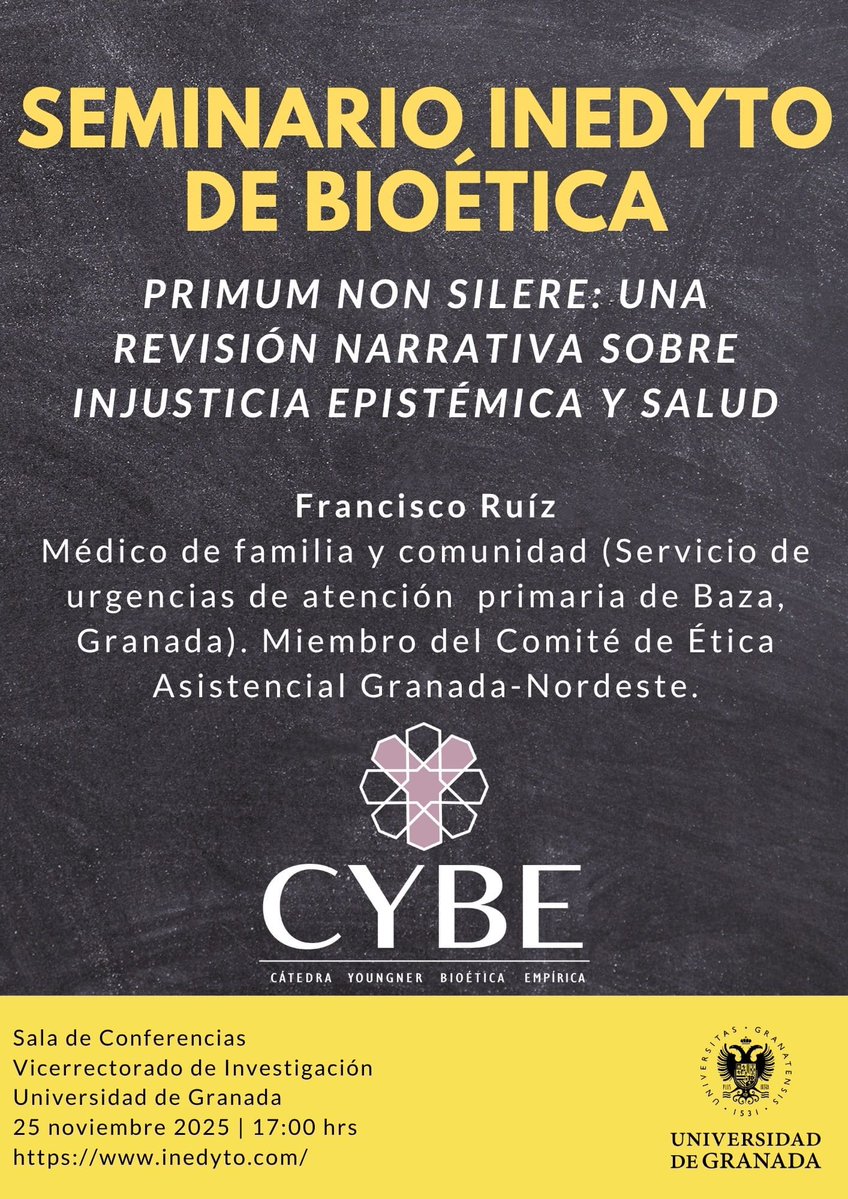

📢 Nueva sesión del Seminario @inedyto de Bioética (SiB) “Primum non silere: Una revisión narrativa sobre injusticia epistémica y salud” Con Francisco Ruiz, médico de familia y comunidad (SUAP Baza) y miembro del CEA Granada-Nordeste. 🗓 Martes 25 de noviembre · 17 h